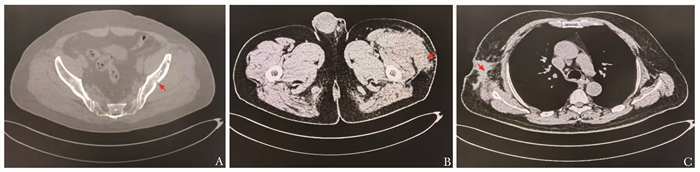

肿瘤性骨软化症68Ga-DOTATATE PET/CT显像特点分析

张雨薇, 景红丽

2023, 2(3): 398-405. DOI: 10.12376/j.issn.2097-0501.2023.03.010